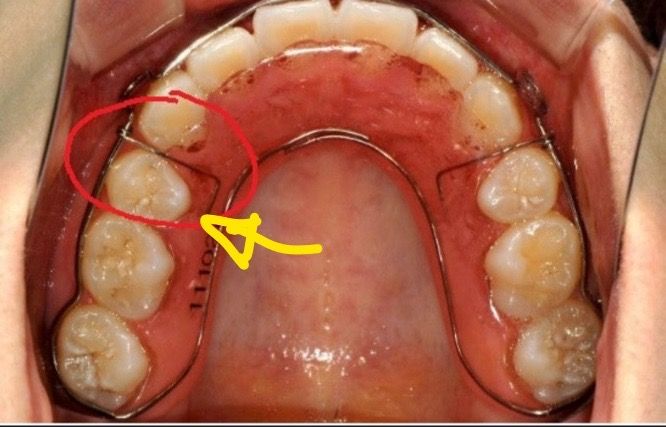

가철식유지장치 틈이 생겨버렸어요 ㅠㅜ

고정식유지장치 제거후 여기에 틈이 생겼는데 괜찮을까요..?ㅠㅠㅠ들뜨는 건 없는데 제거한 후 틈이 생겨 버려가지고 틀어질까봐 무서워서요,,